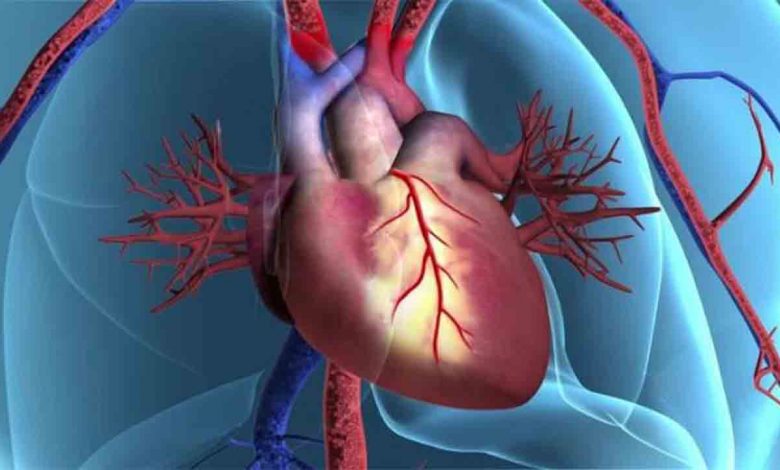

Toplumların gelişmişlik dereceleri arttıkça kalp ve damar hastalıkları daha sık görülür olmuştur. Halen toplumumuzdaki en önemli ölüm sebebi kalp ve damar hastalıklarıdır. Bunların çoğunluğu da kalp krizlerinden olmaktadır. Kalp ve damar hastalıkları için en önemli risk faktörleri tansiyon yüksekliği, şeker hastalığı, sigara ve tütün ürünleri kullanımı, ailevi yatkınlık, kilo fazlalığı ve hareketsiz yaşam tarzıdır. Kalp damar hastalığı tanısı konulduktan sonra yapılan anjiyografi ile hangi damarda ne kadar darlık olduğu tespit edilir ve bu tespit ışığında nasıl bir tedavi uygulanacağı belirlenir. Her zaman bypass ya da her zaman stent diye bir durum söz konusu değildir. Hastanın klinik durumu ve darlıklarını özelliklerine göre hangi tedavinin kullanılacağı değişir. Anjiyografiyi yapan hekim ve kalp damar cerrahisi uzmanı birlikte görüş yürüterek hangi tedavinin hasta açısından daha faydalı olduğunu belirler.

Özellikle şeker hastalığı varlığı, daha önce stent takılıp tekrar daralmış olan damarlarda ve küçük damar çapı durumlarında öncelikle ilaç kaplı olan stentler tercih edilmektedir. Bu vakalarda ilaçsız stentler daha kısa sürede tekrar tıkanabimektedirler. Bu riski göze almamak ve en fazla hasta memnuniyeti açısından imkânı olan hastalarda ilaçlı stentler tercih edilmelidirler. Diğer durumlarda ilaç salgılamayan stentler kullanılırlar. Eğer hastalıklı damarlar stent takılarak tedavi edilemeyecek gibi görünmekteyse, birlikte bir kapak hastalığı var ve bu kapak ameliyat ile değişecekse, kalp adalesinin cansız kısmı mevcut ve bu ameliyatla çıkarılacaksa, ritm bozukluğu yapan bir yer mevcut ve ameliyatla düzeltecekse o zaman hastaya bypass ameliyatı daha uygun bir tedavi seçeneğidir.

Stent ve balon işleminden sonra hekim arkadaşın size tavsiye ettiği ilaçları düzgün olarak kullanmak hayati öneme sahiptir. Özellikle kan sulandırıcı ilaçlar stentin içinde pıhtı oluşumunu azaltarak yeniden tıkanmasını engellemektedir. Doktorunuz kesmedikçe başka hiç bir nedenle ilaç tedavisini kesmemek ve değiştirmemek gerekmektedir. Bazen anjiyografi esnasında kan damar dışına çıkarak o bölgede küçük morartılar yapabilmektedir, bunlar önemli değildirler. Birkaç hafta içinde yok olup giderler. Anjiyografi yapılan kasık ya da kol bölgesinde ilk günlerde ağrı oluşabilir ama ağrı uzarsa ve dayanılmaz boyuta gelirse, şişlik ve morarma başlarsa, bu anjiyografi deliğinin olduğu uzuvda ağrı ve renk değişikliği başlarsa mutlaka hastaneye başvurmak gerekir. İşlem sonrasında yeniden göğüs ağrısının başlaması stentin ya da balon bölgesinin yeniden tıkandığını ifade edebilir. Mutlaka hızlı bir şekilde doktora başvurmak gerekir. Bu durumun en sık sebebi kan sulandırıcı olarak verilen ilaçların kesilmesi ya da aksatılmasıdır. Bu hastalarda stent içine bakabilmek için yeniden anjiyografi yapılması gerekmektedir ve gerekli olan girişimsel tedavi ya da ilaç tedavisi bu esnada kararlaştırılmaktadır.